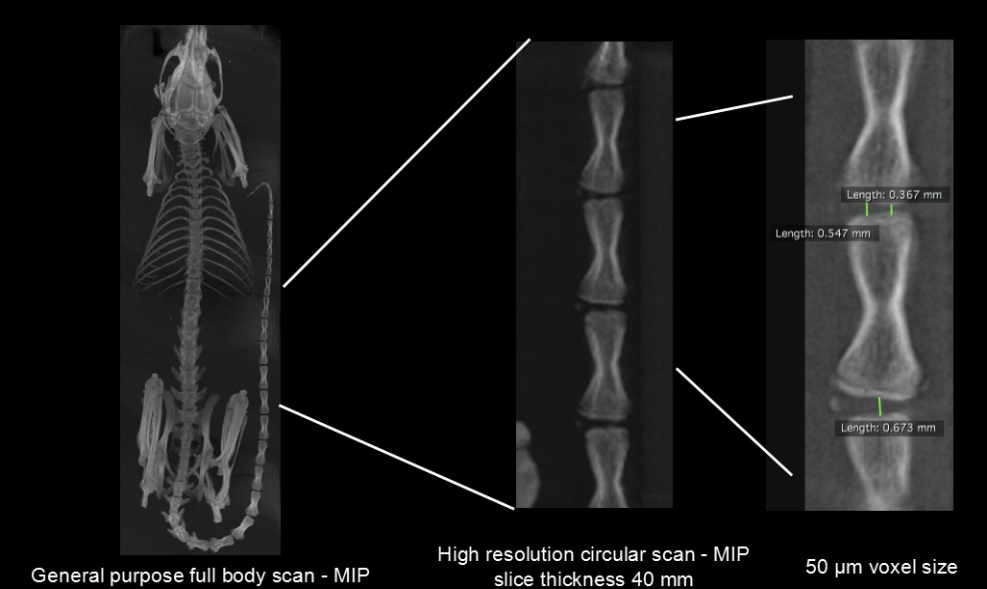

In vivo measurement of rat tail vertebrae: high resolution ring acquisition, acquisition time: 2min3s, ISRA reconstruction, 50µm voxel size.

In vivo measurement of spinal vertebrae in rats: high definition ring acquisition, acquisition time: 4min, FDK reconstruction, 50 and 20µm voxel size.